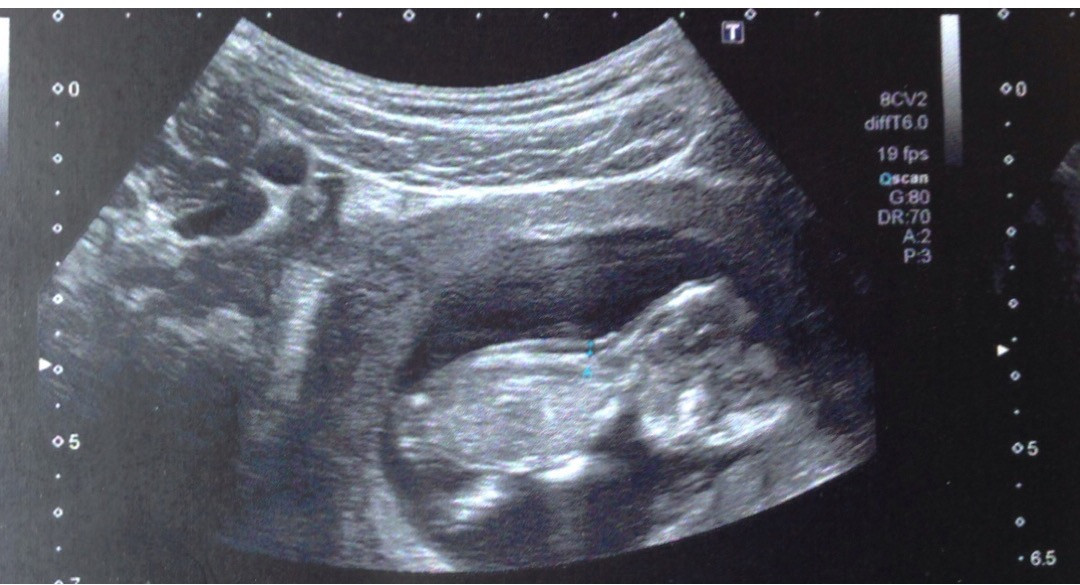

Decidi partilhar com vocês a primeira fotografia do nosso Gui,

o nosso Principezinho tão desejado e amado!

Aqui ainda era bem pequenino, tinha apenas 12 semaninhas e 2 dias,

lembro-me tão bem deste dia...

Hoje com 35 semanas e 4 dias, pesa 2561gr e mede quase 49cm.